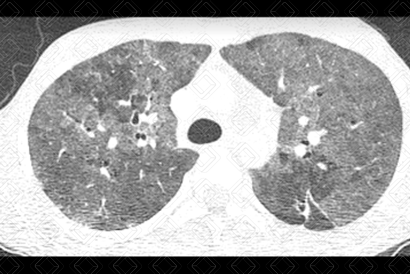

Texto alternativo para a imagem Créditos: Dra. Elazir Mota - Rio de Janeiro/RJ

Descrição da lesão: Tomografia computadorizada do tórax. Extensas opacidades em vidro fosco distribuídas difusamente pelo parênquima pulmonar associado a pequenos cistos à direita (setas vermelhas), num paciente sexo masculino, 15 anos, SIDA - transmissão vertical. A hipótese de pneumocistose deve ser sugerida e, no caso descrito, foi confirmada.

• Tomografia computadorizada do tórax: Opacidades em vidro fosco, difusamente distribuídas pelo parênquima, são os achados mais comumente observados. A ordem decrescente de acometimento: opacidades em vidro fosco, as consolidações alveolares, as alterações das vias aéreas (dilatações brônquicas e espessamento de paredes brônquicas), o espessamento de septos interlobulares, eventualmente formando o padrão de pavimentação em mosaico, as lesões císticas e os nódulos. Diante de uma história clínica adequada (paciente HIV+), o achado tomográfico de áreas em vidro fosco dispersas pelo parênquima associado a cistos pulmonares é muito sugestiva de pneumocistose.